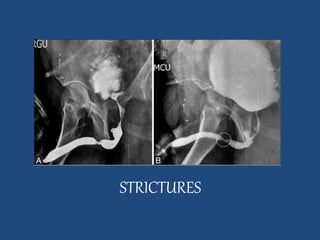

RETROGRADE URETHROGRAPHY

INDICATIONS

1. Stricture

2. Diverticula

3. False passages in urethra

CONTRAST MEDIUM

60% Urograffin or NaI

TECHNIQUE

• Preliminary film of bladder base & urethra

• Film in oblique position- bladder neck &urethra

• Brodney clamp introduction

• Radiographs during injection/distension of urethra

• Procedure repeated in other oblique positions &

appropriate films are taken

STRICTURES